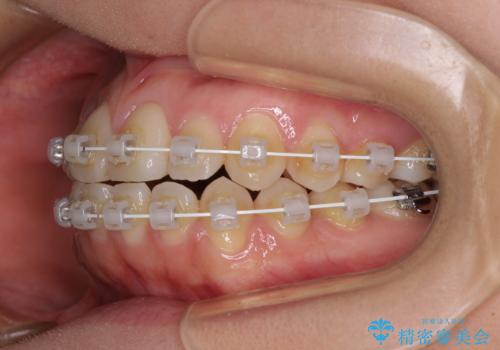

受け口傾向の非抜歯矯正であったため、インビザラインによる矯正治療をお勧めしましたが、自己管理が面倒であるとのことで、ワイヤー装置にて行うこととしました。

右奥の歯が180度回転していることで、噛む度にワイヤーに無理な力がかかったようで、頻繁にワイヤーが切れてしまいました。また、下顎を後方に移動させるためのアンカースクリューも脱離することが多く、治療期間が長くなってしまいました。